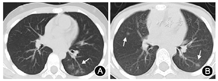

15例患儿中,6例初诊胸部CT影像未见明确病灶;9例出现肺部炎性浸润,考虑为新型冠状病毒肺炎(COVID-19)。9例COVID-19的CT影像表现:病变大多位于胸膜下,表现为胸膜下斑片状影或者单个结节状磨玻璃影,部分边缘可见晕征;其中病变表现为小结节磨玻璃影7例,病变表现为斑片影2例(图1);其中病灶局限于单个叶段的有4例,局限于2个叶段的有4例,超过2个叶段的有1例。

15例患儿治疗3~5 d后复查病毒核酸、外周血血常规及胸部CT:白细胞计数偏低3例,白细胞计数正常12例。病毒核酸转阴性者6例,其中2例患儿胸部CT炎症较前吸收减少(图2),3例患儿肺部仍未见病灶,1例患儿胸部CT炎症无明显变化;病毒核酸仍阳性者9例,其中6例患儿胸部CT炎症表现较前无明显变化,3例患儿复查胸部CT新见炎症表现,均表现为小结节磨玻璃影且均局限于单个叶段(表1)。